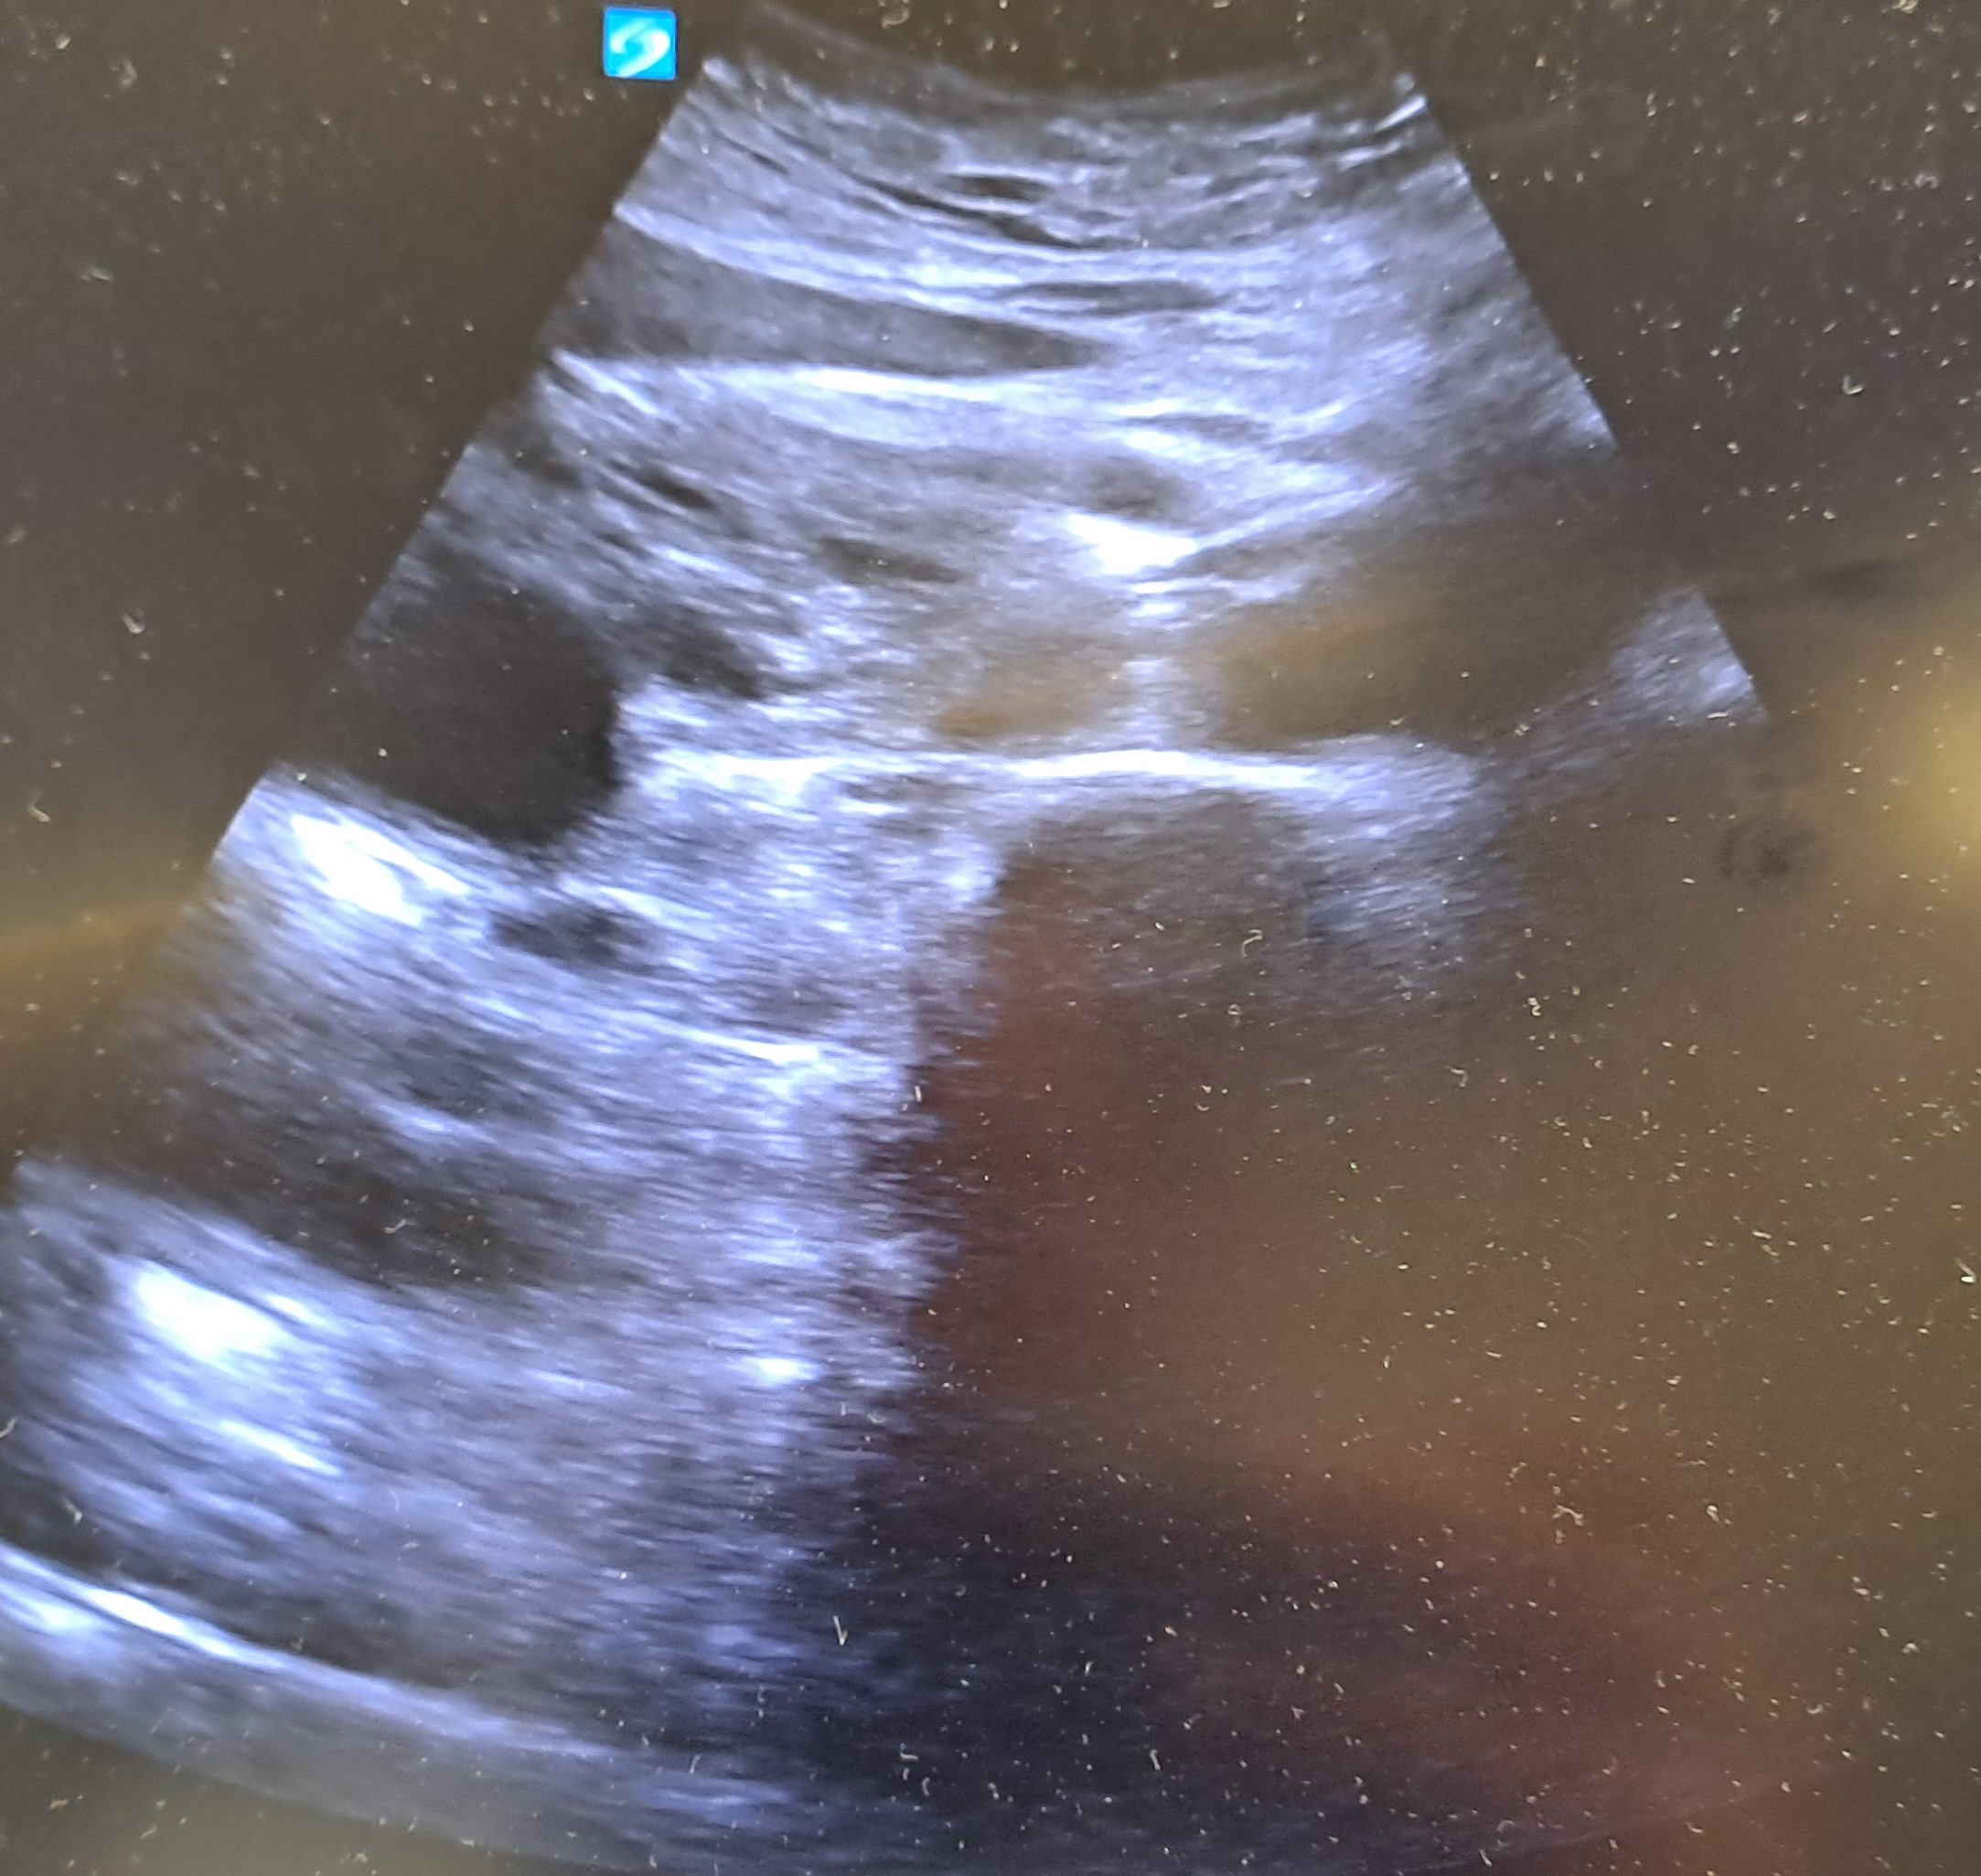

Ecografía abdominal: Hígado de bordes lisos y homogéneos, no lesiones ocupantes de espacio. Vesícula biliar no dilatada, no engrosamiento de paredes. Presencia de múltiples lesiones anecoecogénicas redondeadas en cabeza de páncreas, la mayor de unos 5cm de diámetro, no se objetivan lesiones en cuerpo y no se visualiza cola del páncreas. Riñones: no alteraciones en la ecogenicidad o tamaño.